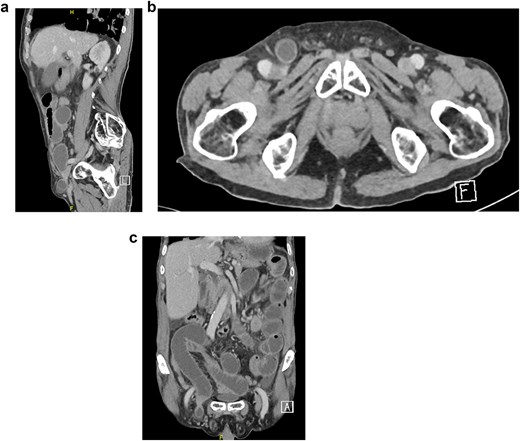

Bloodwork was normal except for a leukocyte count of 15 × 109/l. A chest x-ray was unremarkable. An abdominal X-ray showed dilated small bowel loops with multiple air-fluid levels. Abdominal computed tomography (CT) with intravenous (IV) contrast confirmed a right-sided direct inguinal hernia with small bowel obstruction, preserved bowel enhancement, and no extraluminal air. However, a femoral hernia was not identified on imaging before surgery or on retrospective review postoperatively (Fig. 1a–c). The patient received 2 g of IV cefazolin preoperatively.